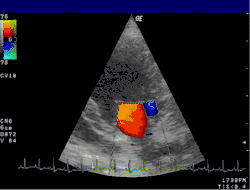

Цветовое доплеровское картирование (ЦДК)

Основано на кодировании в цвете значения доплеровского сдвига излучаемой частоты. Методика обеспечивает прямую визуализацию потоков крови в сердце и в относительно крупных сосудах. Красный цвет соответствует потоку, идущему в сторону датчика, синий — от датчика. Темные оттенки этих цветов соответствуют низким скоростям, светлые оттенки — высоким. Недостаток: невозможность получения изображения мелких кровеносных сосудов с маленькой скоростью кровотока. Достоинства: позволяет оценивать как морфологическое состояние сосудов, так и состояние кровотока по ним.

Кардиология, сосудистая и кардиохирургия

Эхокардиография (ЭхоКГ) — это ультразвуковая диагностика заболеваний сердца. В этом исследовании оцениваются размеры сердца и его отдельных структур (желудочки, предсердия, межжелудочковая перегородка, толщина миокарда желудочков, предсердий и т. д.), наличие и объём жидкости в полости перикарда, состояние клапанов сердца, а также, в доплеровском режиме, кровоток в сердце и магистральных сосудах. С помощью специальных расчетов и измерений эхокардиография позволяет определять массу миокарда, сократительную способность сердца (фракцию выброса, сердечный выброс и др.). Обычно ЭхоКГ проводится через грудную клетку (трансторакально), также существует чреспищеводная ЭхоКГ (ЧП-ЭхоКГ), когда специальный эндоскопический датчик помещается в пищевод. ЧП-ЭхоКГ позволяет лучше рассмотреть сердце, так как датчик располагается к сердцу ближе, чем при обычной ЭхоКГ и поэтому становится возможным использовать датчик с более высокой частотой ультразвука, что повышает разрешающую способность изображения. Также существуют специальные высокочастотные интраоперационные датчики, которые помогают во время операций на сердце.